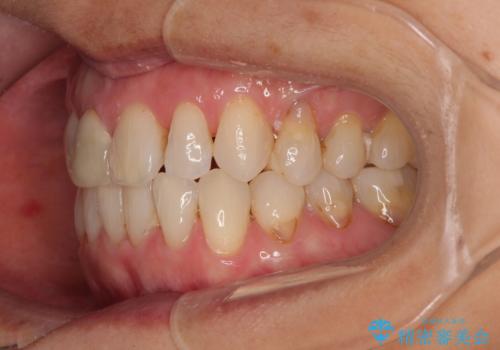

- 前歯のデコボコと口を開けたときに見える銀歯を気にして来院された患者様です。

ある程度デコボコが解消されれば大丈夫とのことで、インビザライン・モデレートパッケージを利用して歯列を整えて行くこととしました。

矯正治療後に銀歯をセラミッククラウンなどに置き換えていくと、どうしても後戻りを起こしてしまうため、矯正治療が概ね終了した時点で銀歯を全てセラミックとし、最後に仕上げでインビザラインにを用いて細かいデコボコを改善していくこととしました。

とても明るい口元となり、人目を気にせず、大きく口を開けて笑えるようになりました。